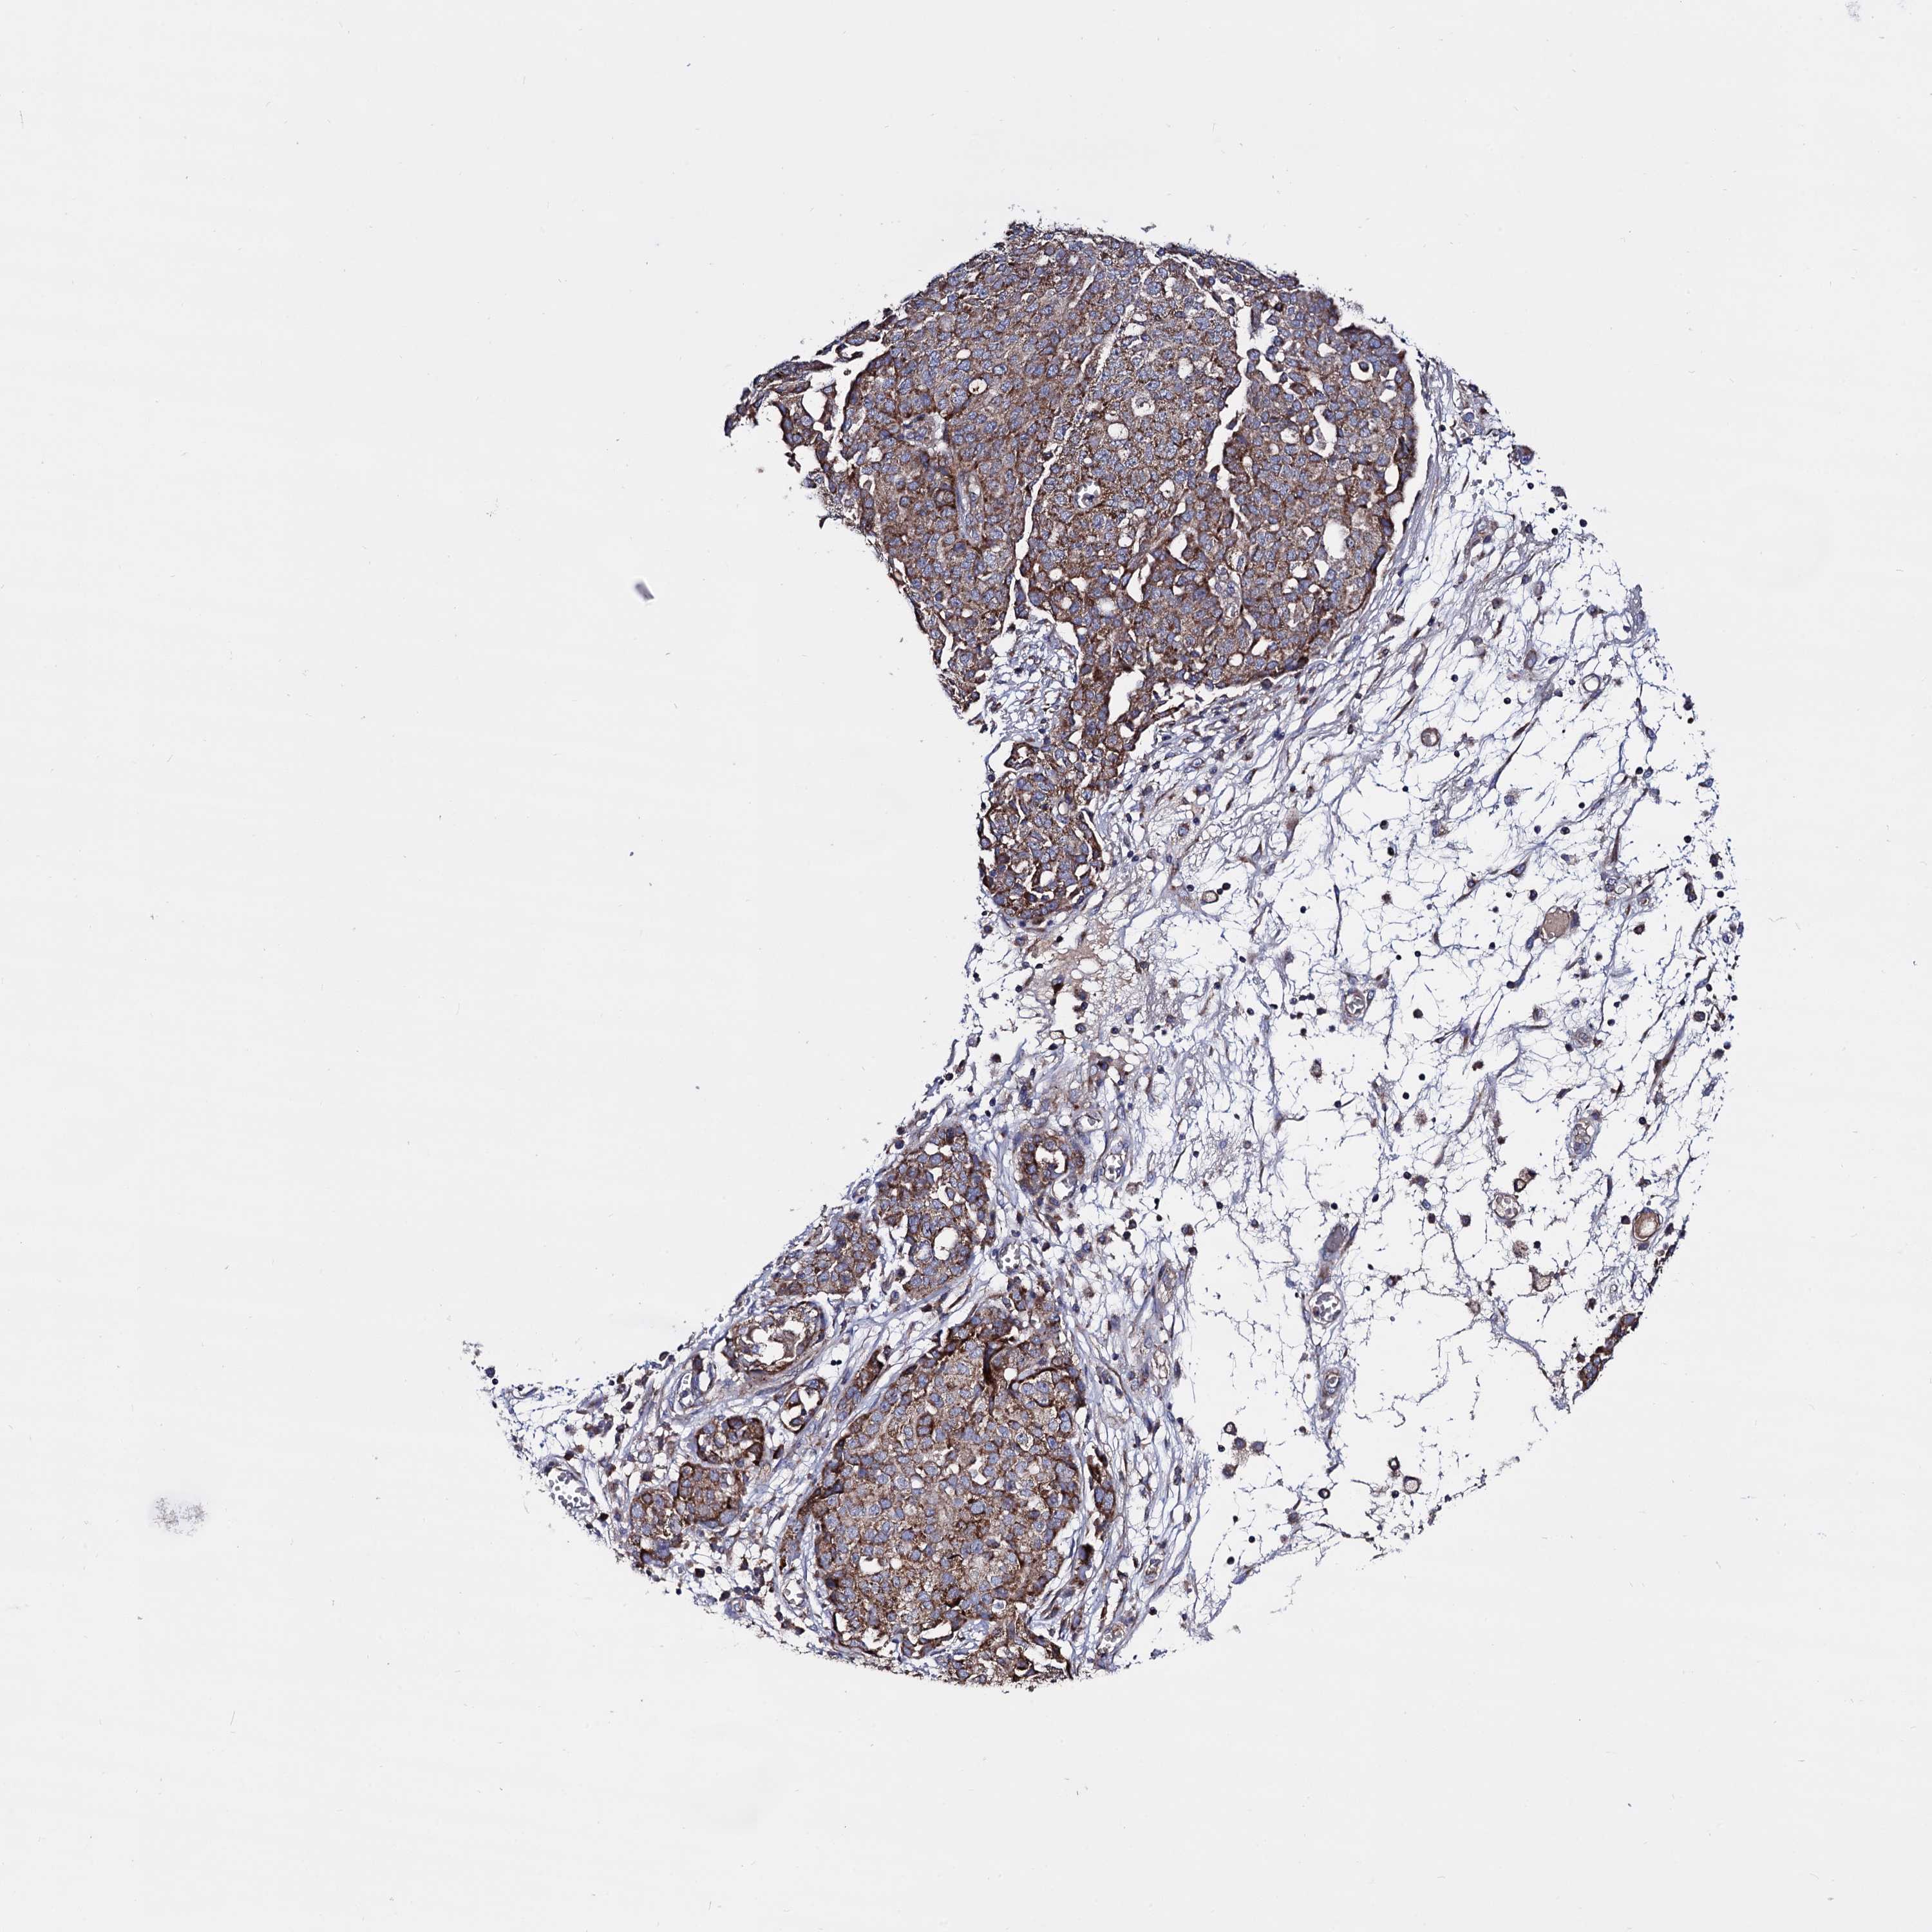

OVARIAN CANCER - Protein expressioni

A mouse-over function shows sample information and annotation data. Click on an image to view it in a full screen mode. Samples can be filtered based on level of antibody staining by selecting one or several of the following categories: high, medium, low and not detected. The assay and annotation is described here.

Note that samples used for immunohistochemistry by the Human Protein Atlas do not correspond to samples in the TCGA dataset.

Antibody stainingi

Antibody staining in the annotated cell types in the current human tissue is reported as not detected, low, medium, or high, based on conventional immunohistochemistry profiling in selected tissues. This score is based on the combination of the staining intensity and fraction of stained cells.

Each image is clickable and will lead to virtual microscopy that enables deeper exploration of all samples and also displays staining intensity scores, fraction scores and subcellular localization as well as patient and tissue information for each sample.

Antibody HPA040845

Staining

High

Medium

Low

Not detected

Intensity

Strong

Moderate

Weak

Negative

Quantity

>75%

75%-25%

<25%

None

Location

Nuclear

Cytoplasmic/membranous

Cytoplasmic/membranous,nuclear

Cystadenocarcinoma, serous, NOS

Carcinoma, endometroid

Cystadenocarcinoma, mucinous, NOS

Carcinoma, NOS